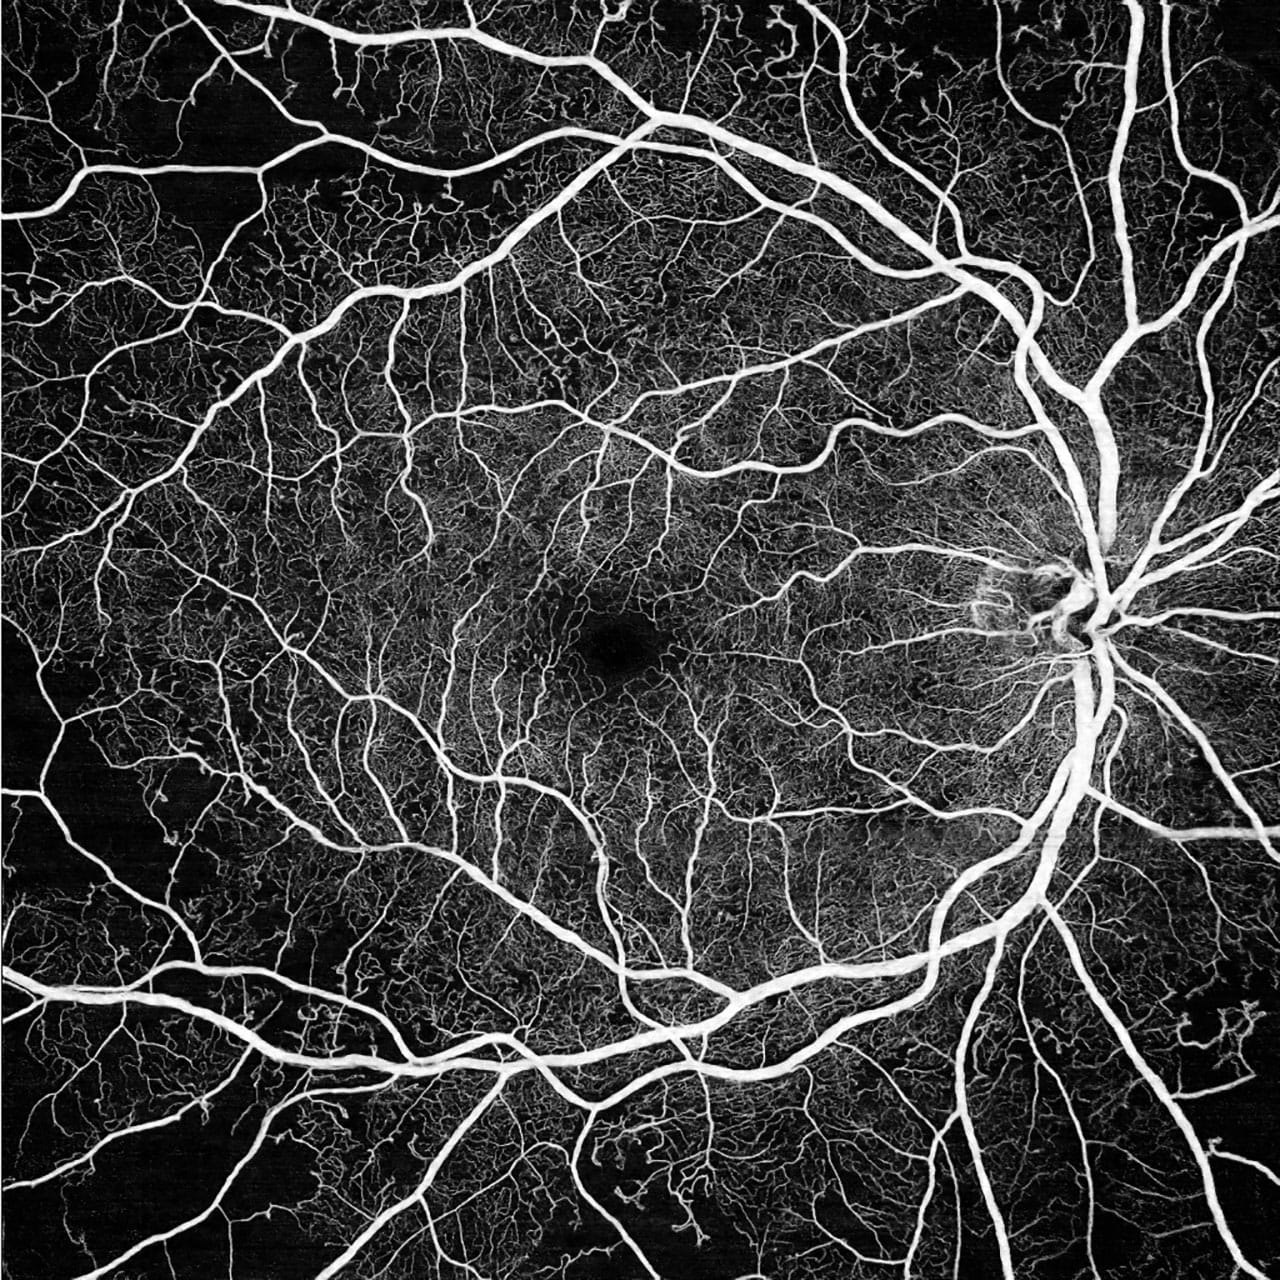

Established in 2018, Southwest Retina Research Center serves the Four Corners area as the region’s only ophthalmic research site. We participate in clinical trials for new investigational treatments, including gene therapies and implantable devices for disease such as Macular Degeneration (wet and dry), Diabetic Retinopathy, and Glaucoma.